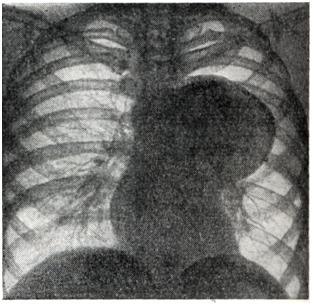

Рис. 3.

Веретенообразная аневризма восходящей аорты и ее дуги с обызвествлением стенки аневризмы (рентгенограмма).

Аневризмы восходящей аорты обычно хорошо определяются в виде выпячиваний на правом контуре сосудистой тени в прямой проекции (рис. 3) и на переднем контуре — в левом косом и боковом положениях. Гораздо реже аневризма располагается на левой стенке восходящей аорты и образует выпячивание слева. Аневризмы дуги аорты (рис. 4) в прямой проекции обычно имеют вид массивной тени над изображением сердца, а в левом переднем косом положении проецируются на область дуги аорты. Аневризмы нисходящей аорты дают добавочные тени по левому контуру сосудистой тени (книзу от первой дуги) в прямой проекции и проецируются на ретрокардиальное пространство и тень позвоночника в косых положениях. Бывают множественные аневризмы аорты.